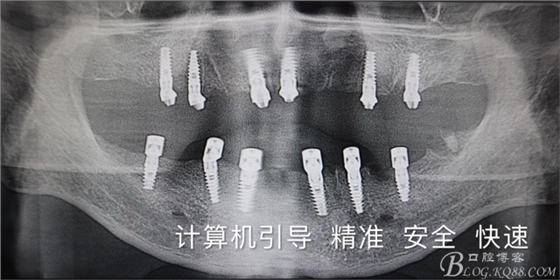

首頁牙科種植 四塊導板.全口種植.即刻負重

四塊導板.全口種植.即刻負重